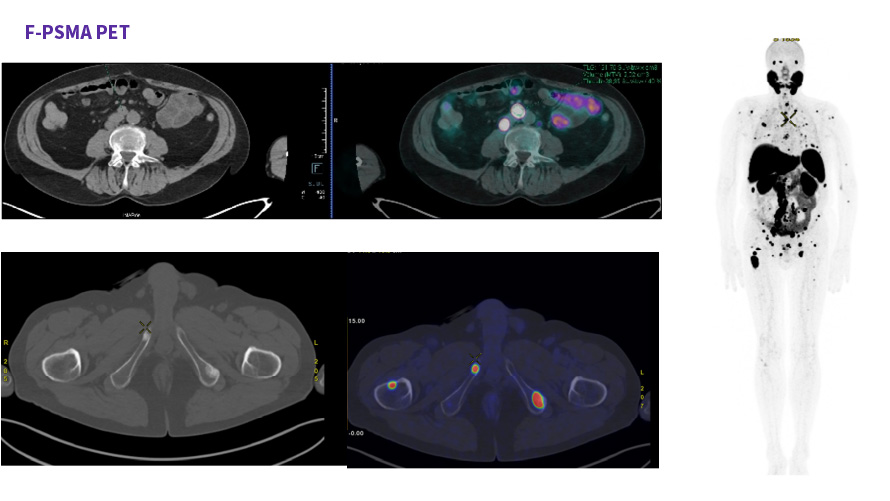

Caso condiviso da Saima Mushtaq

Paziente con anamnesi di malattia coronarica e pregresso impianto di stent sulla discendente anteriore sinistra.